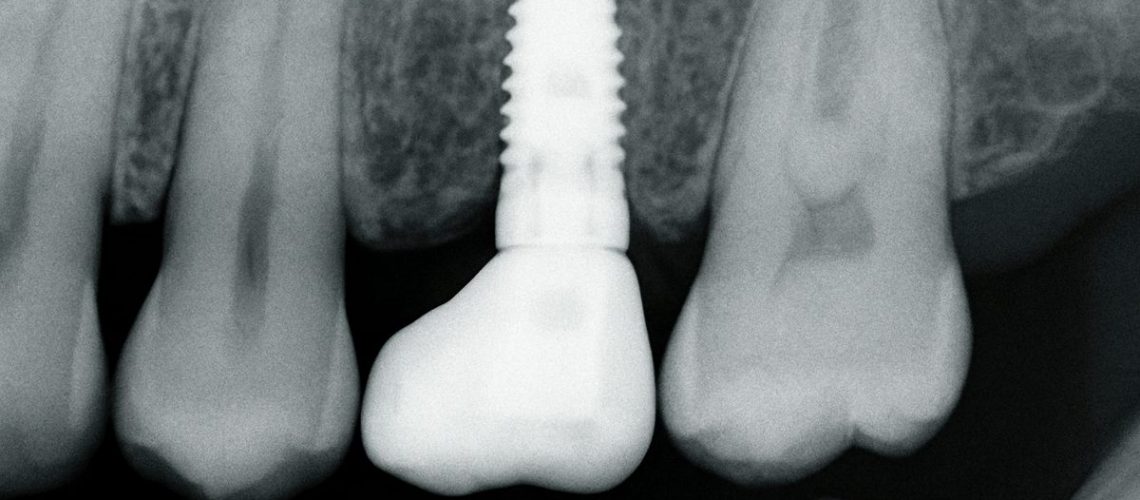

Close up X-Ray showcasing a dental implant seamlessly integrated into the jawbone, replacing a missing tooth. No text on image.

Dental implants replace the tooth root with a titanium post that bonds to bone. Benefits include:

Implant placement is often done with a surgical guide for precise positioning. A temporary tooth may be placed the same day in many cases. Osseointegration — the process where bone fuses to the implant — typically takes several weeks to a few months.

After healing, a custom abutment and crown are made using CAD/CAM milling for a precise fit. The final crown is checked for bite, color, and comfort before being seated.